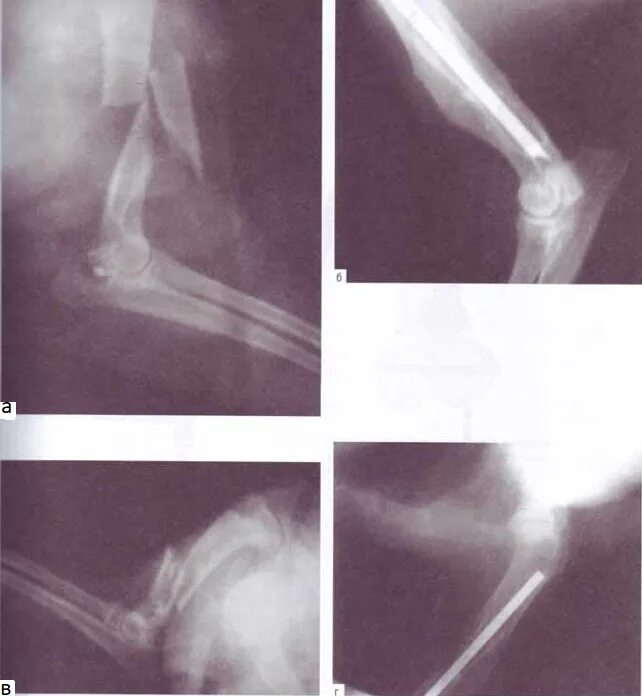

Оскольчатый перелом со смещением